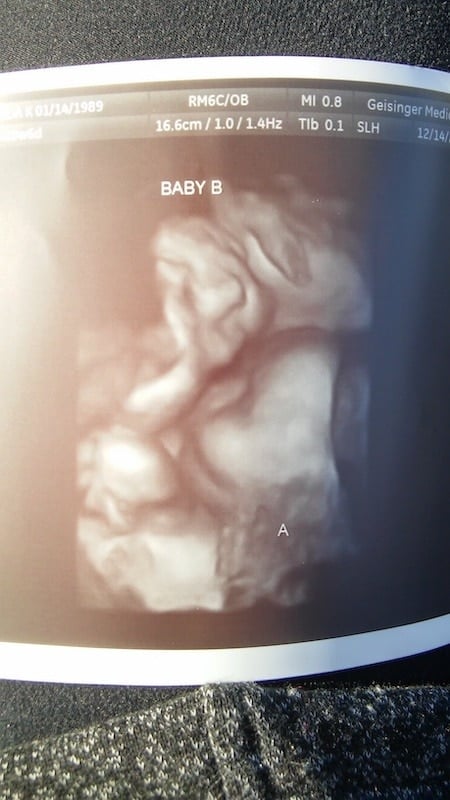

Ultrasound Photos at 22 Weeks Pregnant With Twins